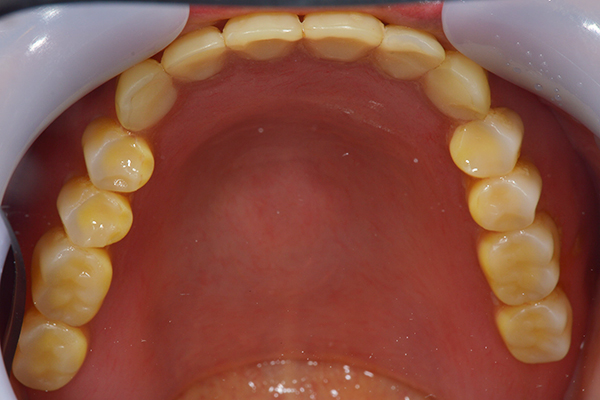

入れ歯は極力薄くするために金属を使用しました。しっかり噛める様にするため、ノンメタルクラスプデンチャーにはしませんでした。

上の入れ歯(表)

上の入れ歯(裏)